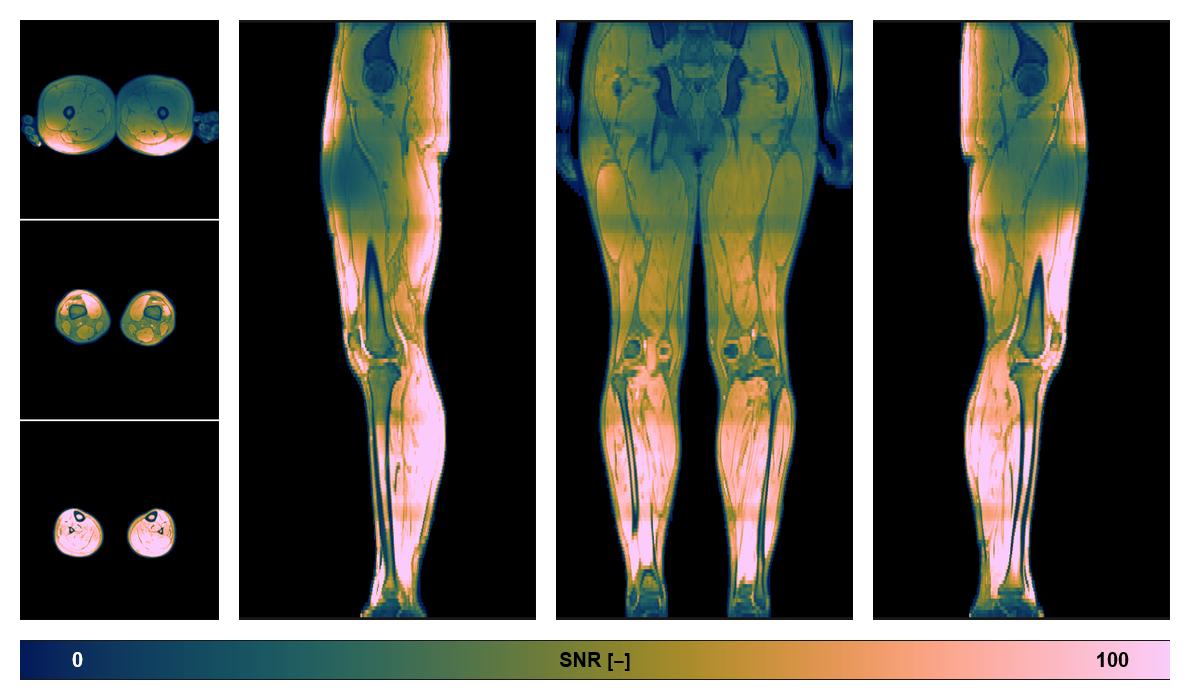

• SNR distribution

The SNR distribution of the dixon data.